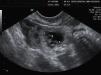

En la ecografía transvaginal se evidenciaron tres vesículas vitelinas con tres polos embrionarios de aproximadamente 3,5mm de LCN y con latidos cardíacos positivos, los tres en un mismo saco enclavado en tercio medio de trompa izquierda (fig. 1). Ambos anejos eran normales. El útero era regular, con la línea endometrial de 7,5mm espesor. En el saco de Douglas había cerca de 25mm de líquido libre (fig. 2).